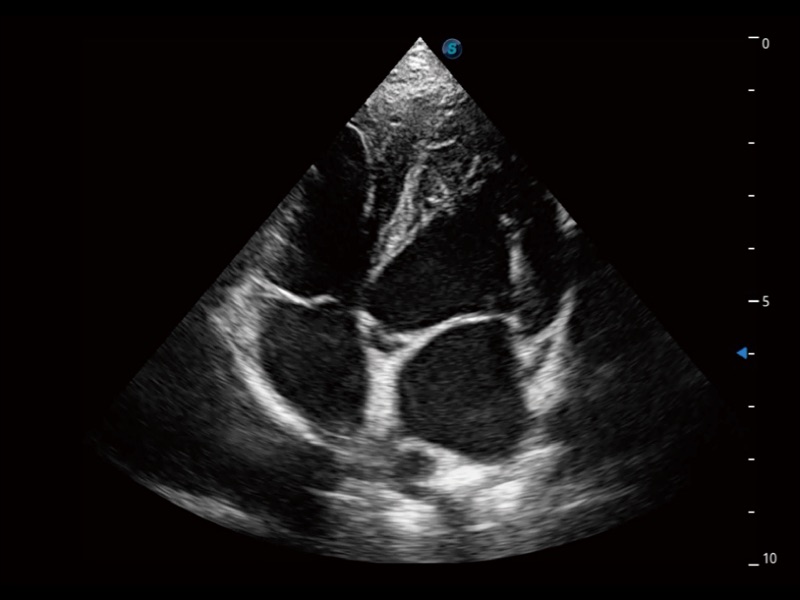

优异的基础图像

(犬)四腔心

(犬)四腔心MQA